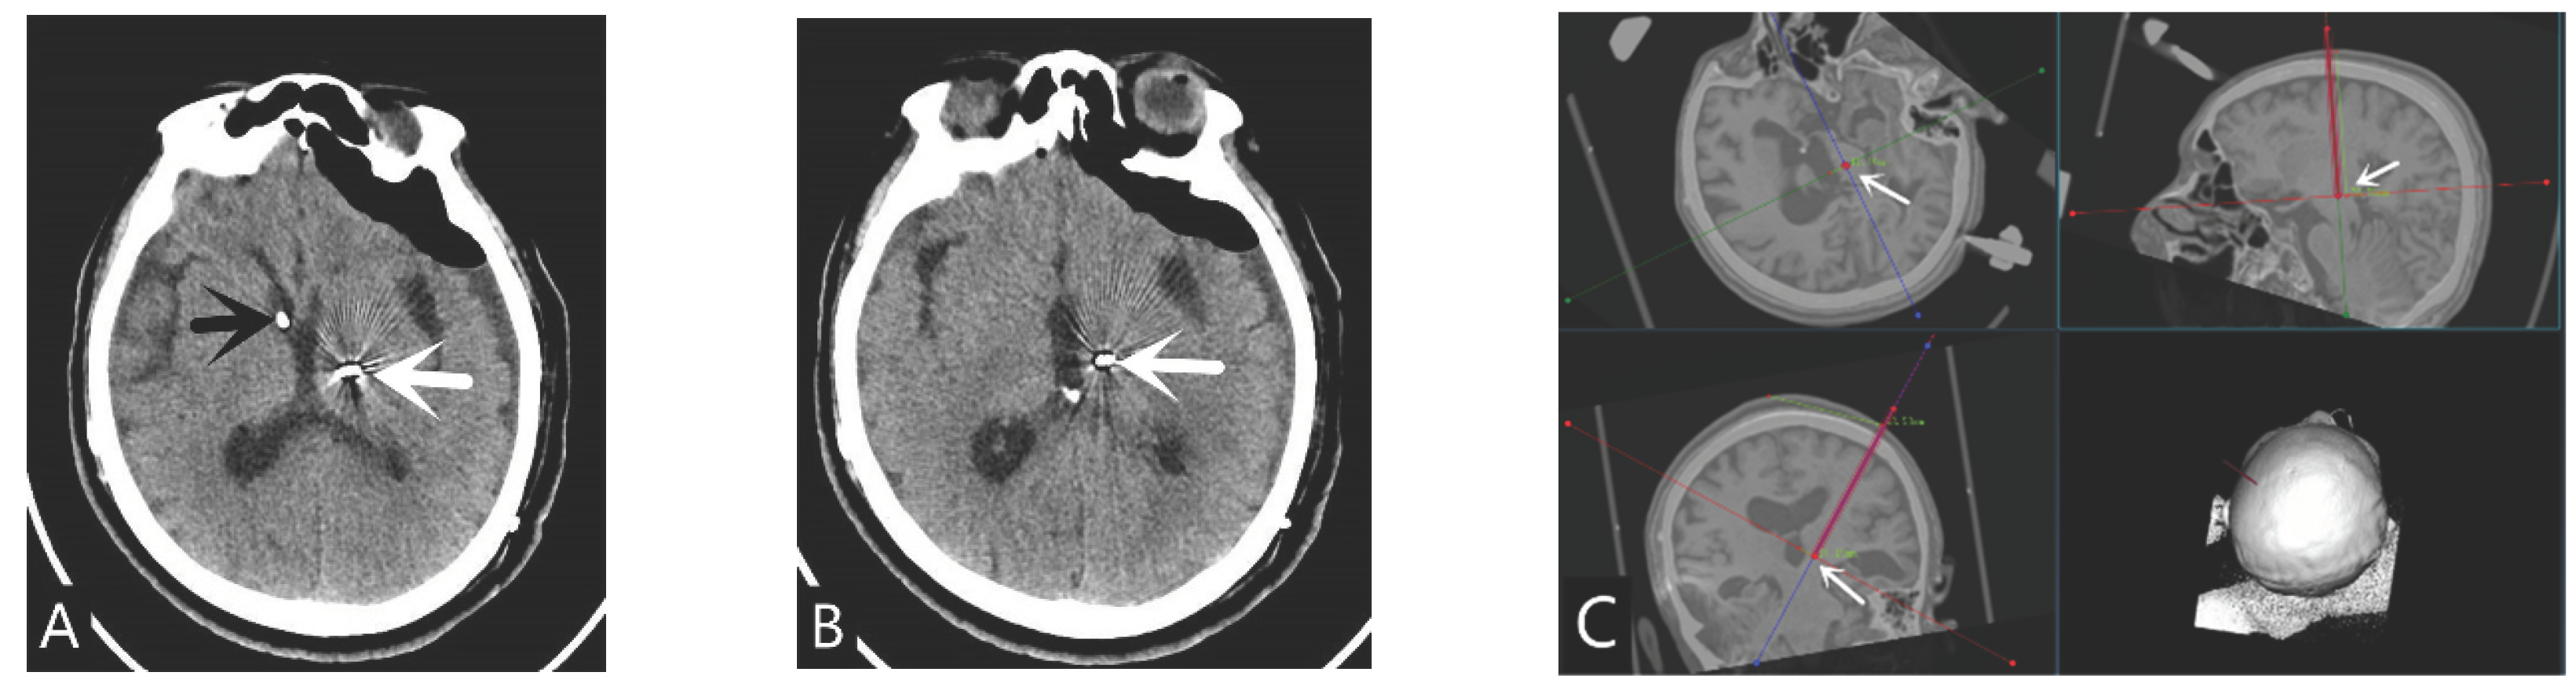

The target of DBS surgery is the bilateral thalamic central midline parafascicular nucleus (CM-pf nucleus). If electrodes cannot be placed on one side due to skull repair or other reasons, only the other side can be placed, and it can be placed on the same side as the ventricular shunt tube (Figure 1). The electrode placement site for spinal cord electrical stimulation is on the dorsal side of the epidural layer at the level of 2-3th in the neck(Figure 2).

Figure 2. High position SCS electrode located at the level of the 2-3th cervical vertebral body. (A) Lateral view of SCS electrode shown on DSA(white arrow); (B) Sagittal CT image of SCS electrode(white arrow); (C) Coronal CT image of SCS electrode (white arrow); (D) Axial CT image of SCS electrode(white arrow).